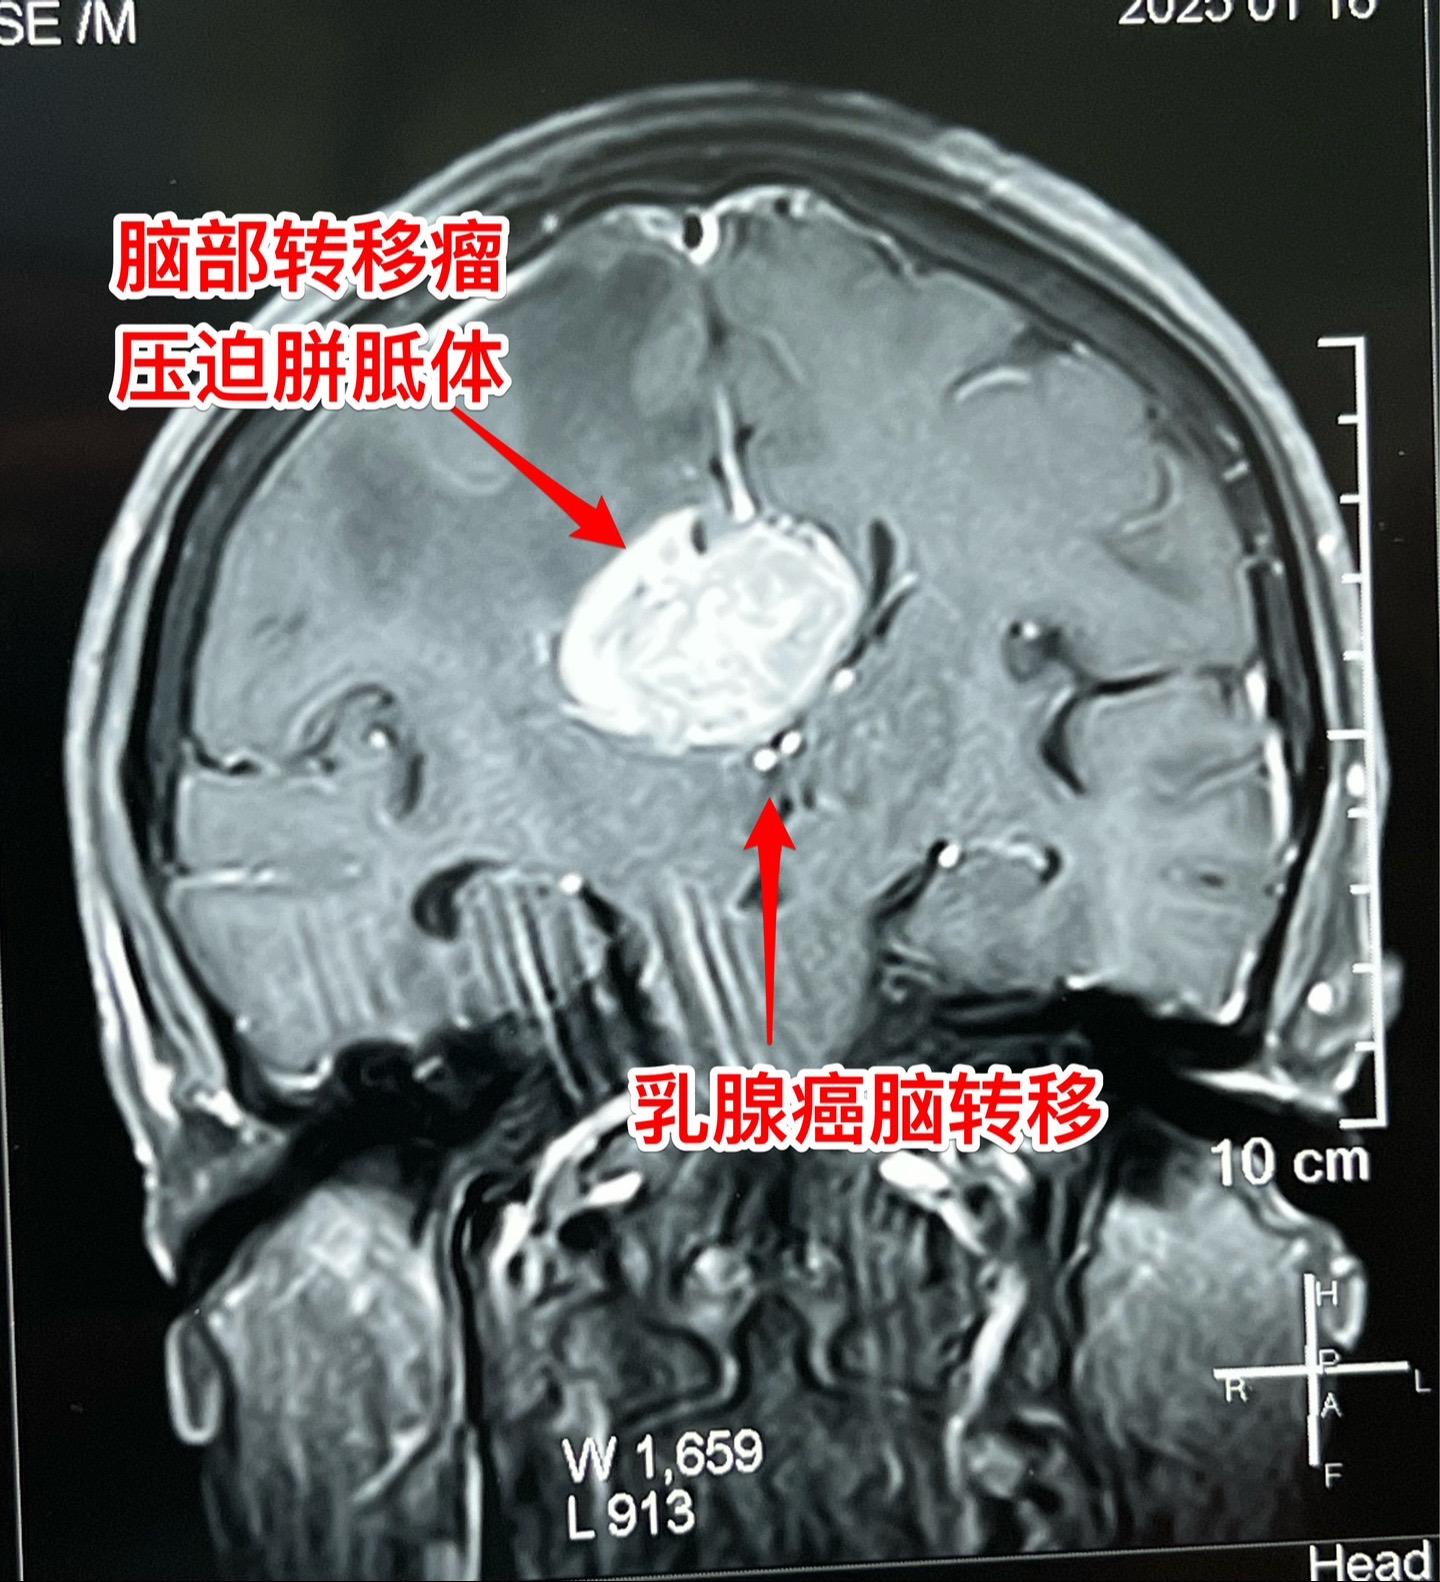

乳腺癌也能转移到脑部。脑部的转移瘤约80%来源于肺癌,绝大多数是腺癌。 乳腺癌发病率虽然低于肺癌,但也很常见。乳腺癌也可能转移到脑部。 这个54岁女性在7个月前先发现 脑部有个瘤,随后发现了乳腺癌,作了乳腺癌切除手术及内分泌治疗。多次复查磁共振显示脑部的瘤体积在增大,而且病人也出现头痛症状,故来作手术。 1月23日作了手术,顺利切除肿瘤。术前病人担忧出现偏瘫症状,手术后并没有出现。 针对这个病随后还需要综合治疗。